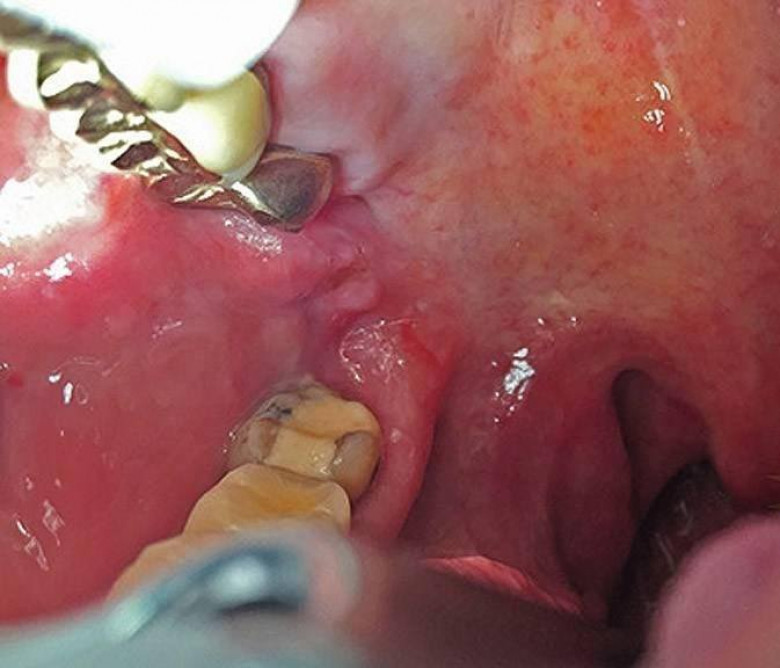

Համբուրգի 65-ամյա բնակչուհին դիմեց բժիշկներին, ասելով, որ չի կարողանում գտնել ատամները լվանալու ժամանակ կորցրած էլէկտրական խոզանակի կտորը: Բժիշկները նախ հետազոտեցին կնոջ ստամոքսն ու աղիները, բայց ոչինչ չհայտնաբերեցին և նրան ուղարկեցին տուն: Բայց մի քանի օր անց կինը կրկին դիմեց հիվանդանոց՝ գանգատվելով, որ ոչինչ չի կարողանում ոչինչ ուտել: Դիմածնոտային վիրաբույժը կնոջ բերանի խոռոչի փափուկ հյուսվածքներում 6 սմ երկարությամբ օտար առարկա նկատեց: Պարզվեց, որ դա հենց ատամի խոզանակի ջարդված կտորն էր: Վիրահատությունից հետո մի քանի օր անց կինը դուրս գրվեց: